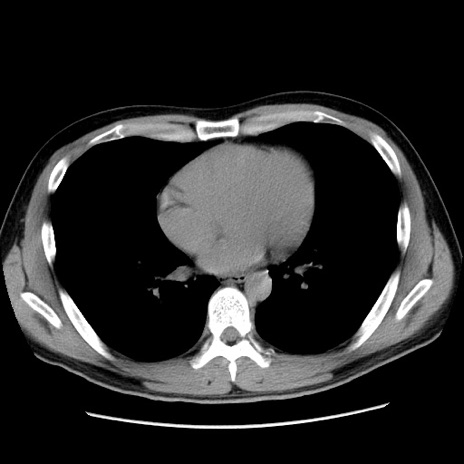

症例36(横断像)

【症例】20歳代 男性

【主訴】心窩部痛

【現病歴】今朝より上腹部痛あり。一旦軽快していたが再度出現したため救急要請。昨日夕に白身の魚を含む刺身を食べた。

【身体所見】BP 136/89mmHg、HR 74/min、BT 37.0℃、腹部:膨満、軟、心窩部に圧痛あり。反跳痛なし、筋性防御なし、腸雑音やや亢進あり。

【データ】WBC 17700、CRP 0.48